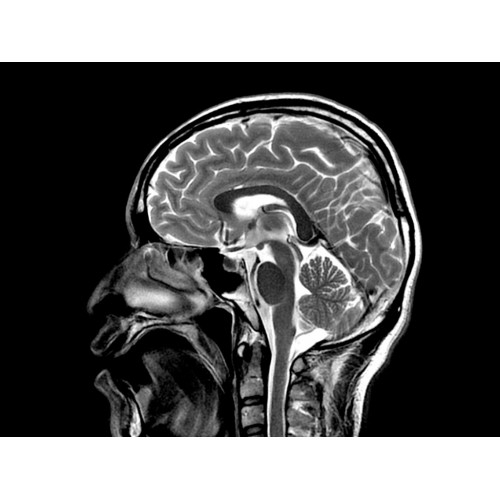

МРТ аппарат GE Optima MR450w 1.5T

МР-томограф с широким туннелем Optima MR450w является настоящей рабочей лошадкой и может эффективно обслуживать большее число пациентов. Томограф обеспечивает одновременно удобство пациента, продуктивность работы, отличное качество изображения. В этой МРТ-системе инженерам компании удалось без компромиссов совместить необходимый объем перемещения с удивительно высоким качеством изображения.

МР-томограф Optima MR450w позволяет получать изображения исключительно высокого качества, которые помогают установить диагноз. Чтобы удовлетворить ожидания клиентов в отношении высокого качества, в МР-томографе Optima MR450w были сохранены дополнительные возможности платформы Discoverу, привнесшие в его работу универсальность и мощь.

• Цифровой РЧ-приемник OpTix — эксклюзивная оптическая РЧ-система увеличивает четкость сигнала и его интенсивность, формируя чистые и резкие изображения.

• РЧ-катушки, оптимизированные для исследования конкретных участков тела — элементы катушек высокой плотности располагаются вокруг исследуемых участков тела и при необходимости обеспечивают расширенный охват и оптимальное качество изображений при каждой процедуре.